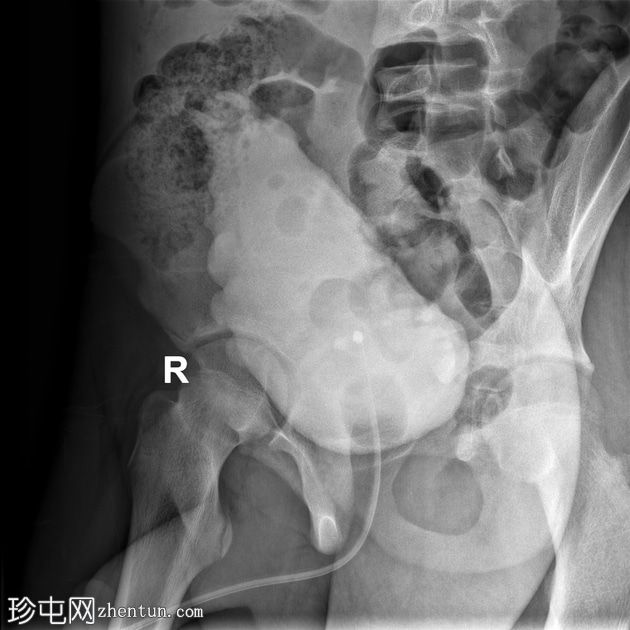

荧光透视

正面

右

通过导尿管注入造影剂后,可见膀胱延长,膀胱壁不规则,呈小梁状,并有多个大小不一的外囊。

排尿后序列中可见残余尿液。

本病例展示了

神经

源性膀胱的临床和放射学特征。